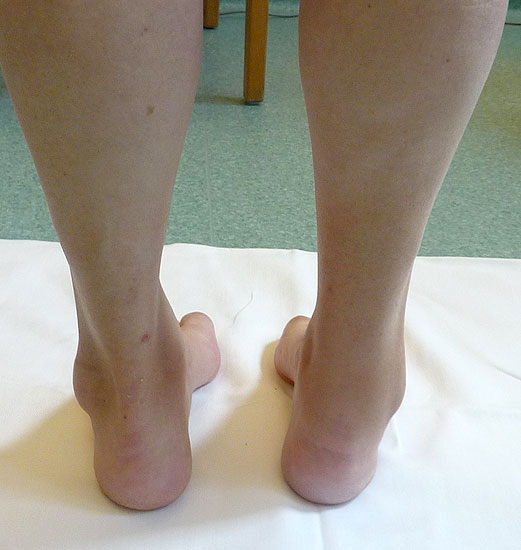

• Ätiologie ungeklärt (Abb. 8 bis 10)

Zum Lesen der Bildbeschreibung und zur Vollansicht bitte die Bilder anklicken. Bilder: A. Simon